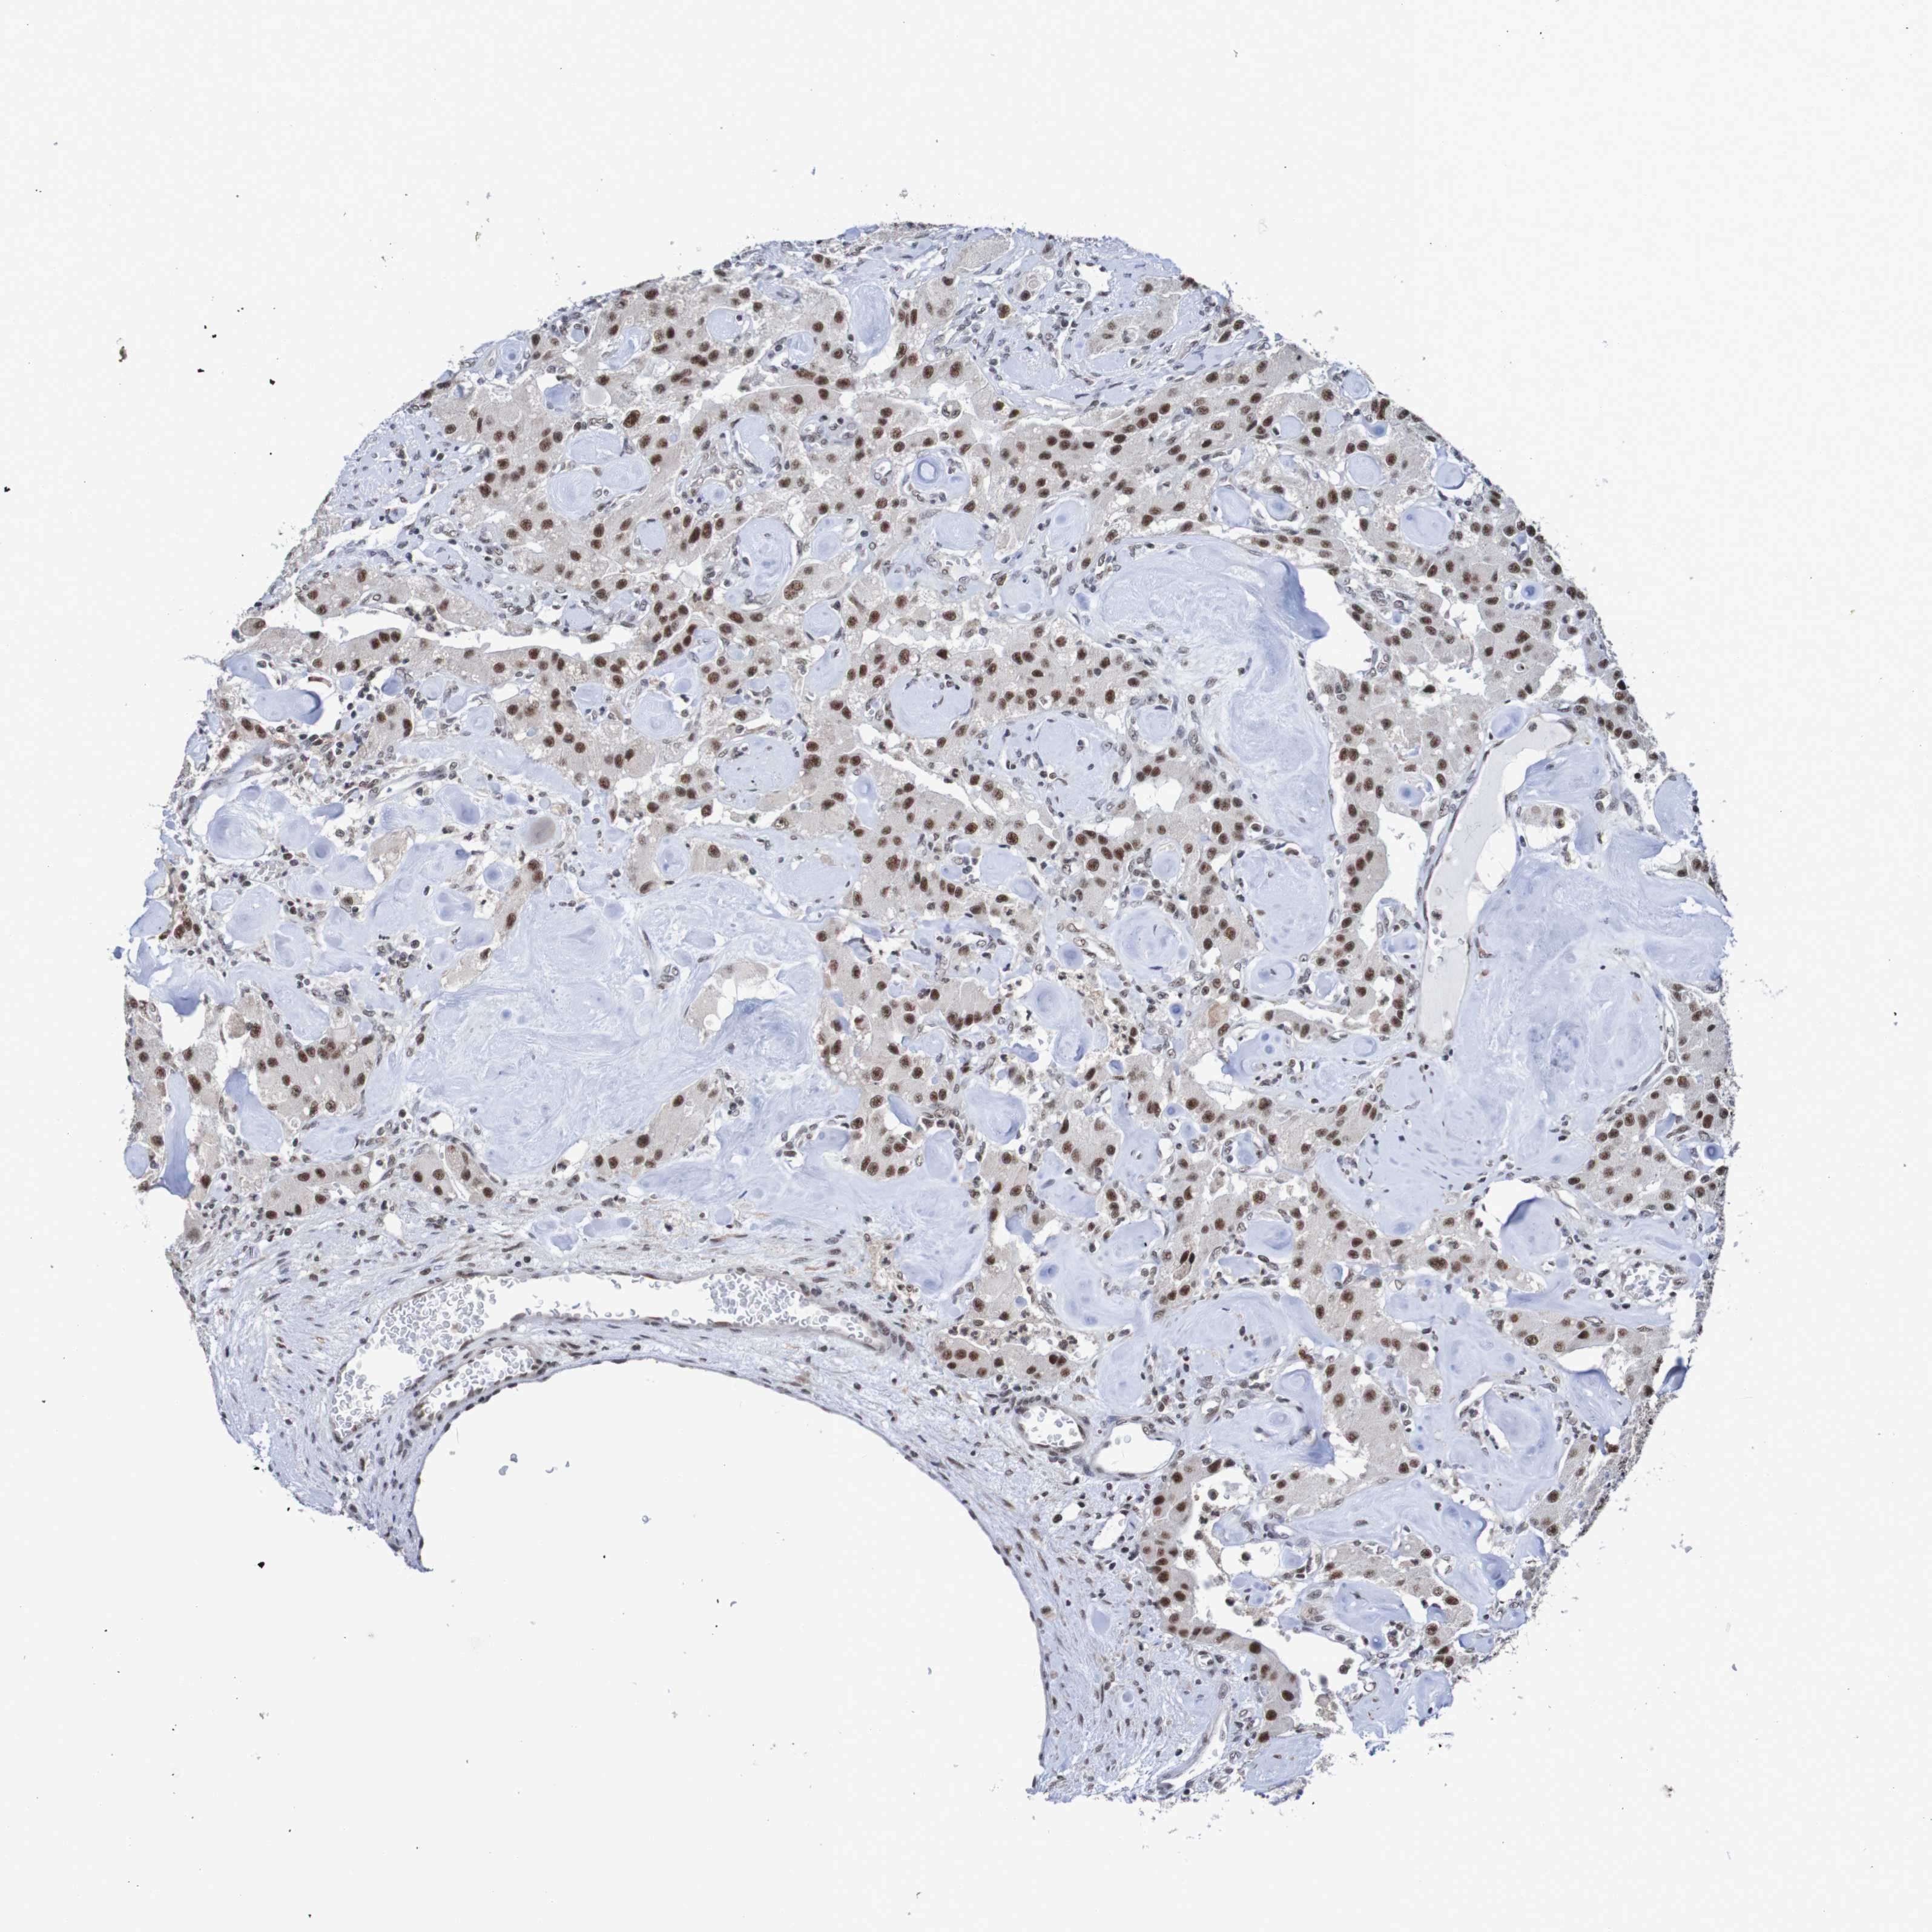

CARCINOID - Protein expressioni

A mouse-over function shows sample information and annotation data. Click on an image to view it in a full screen mode. Samples can be filtered based on level of antibody staining by selecting one or several of the following categories: high, medium, low and not detected. The assay and annotation is described here.

Each image is clickable and will lead to virtual microscopy that enables deeper exploration of all samples and also displays staining intensity scores, fraction scores and subcellular localization as well as patient and tissue information for each sample.

Antibody HPA006302

Staining

High

Medium

Low

Not detected

Intensity

Strong

Moderate

Weak

Negative

Quantity

>75%

75%-25%

<25%

None

Location

Nuclear

Cytoplasmic/membranous

Cytoplasmic/membranous,nuclear

Carcinoid, malignant, NOS